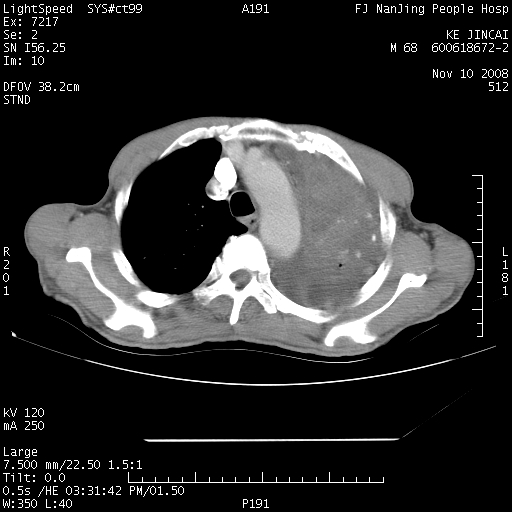

是个很有看头的病例,咋人气那么不旺?没多少人兴趣呢?这个病例几大怪:1   恶性肿瘤侵犯心肌左房怪,心肌一般不会被恶性肿瘤侵犯吧?2   左下肺均匀实变怪,内无含气,有别一般不张实变,含气肺泡完全为液体取代,而非一般不张实变的肺萎陷,冷不丁还以为是肿大的脾脏3   肿瘤本身怪,像tb肺不张4   这么有看头的病例没人气怪。呵呵。

左肺恶性肿瘤侵犯肺动脉,左心房内瘤栓,胸膜转移。

左肺恶性肿瘤侵犯肺动脉,左心房内瘤栓,胸膜转移,少见,学习了。